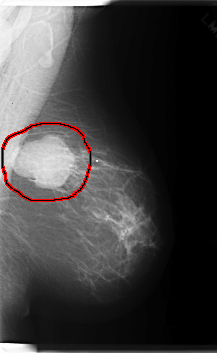

FILE: C_0219_1.LEFT_MLO.OVERLAY

TOTAL_ABNORMALITIES 1

ABNORMALITY 1

LESION_TYPE MASS SHAPE LOBULATED MARGINS CIRCUMSCRIBED

ASSESSMENT 5

SUBTLETY 5

PATHOLOGY MALIGNANT

TOTAL_OUTLINES 1

BOUNDARY

LEFT_MLO LINES 6000 PIXELS_PER_LINE 3680 BITS_PER_PIXEL 12 RESOLUTION 50 OVERLAY